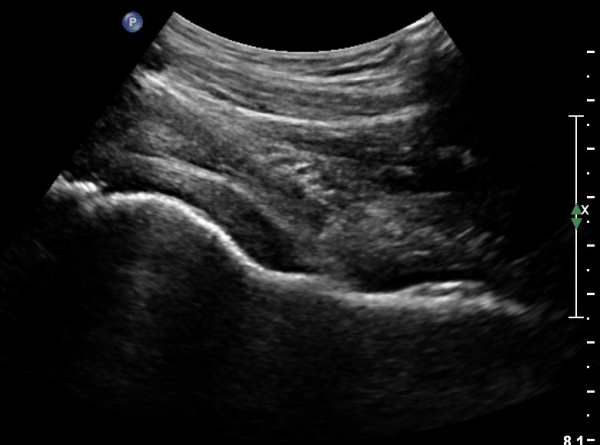

[¾ûµ¢ÀÌ] °í°üÀý Ãæµ¹ÁõÈıº¿¡ÀÇÇÑ È°¾×¸·¿° ÁÖ»çÄ¡·á

ÃÊÀ½ÆÄ °Ë»ç